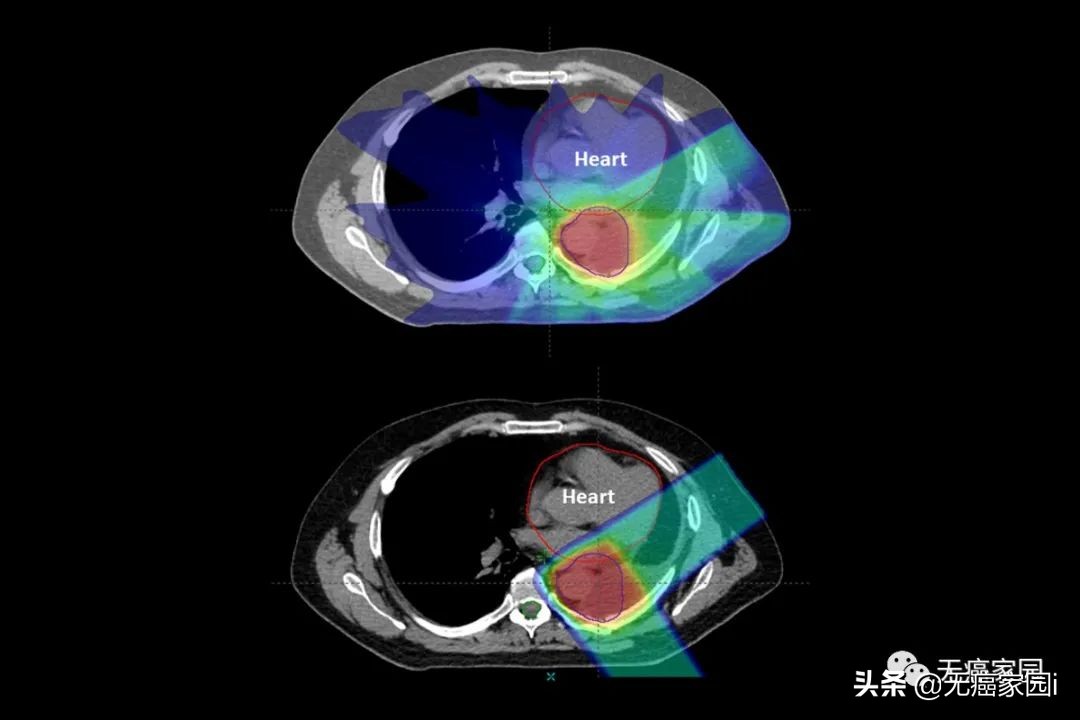

图中病例为肺部肿瘤,质子治疗(底部)在击中肺部肿瘤后停止,X射线(顶部)由光子组成,这些粒子会穿过身体并损伤健康组织(图中为心脏)

结果显示, 质子治疗组一年的总体生存率为83%, 而 X射线放疗组为81% ,并无明显差异。

但两种疗法的副作用差异十分明显:在90天内, 质子治疗组中有45名患者 (11.5%) 出现了严重的副作用症状,而X射线放疗组有301名患者(27.6%) 在同一时期出现了严重副作用症状。

这种差异还是在质子治疗组患者平均年龄更大且存在更多医疗问题情况下出现的。 研究人员称,剔除这些差异因素影响, 接受质子治疗的患者在90天内出现严重副作用症状的风险要比接受X射线放疗的患者低67%(2/3) 。